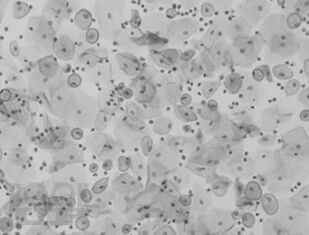

Vulva diseases. Risk factors, diagnosis, prevention, treatment

The study guide provides information about epidemiology, risk factors, diagnosis, prevention, and treatment of benign and malignant vulva diseases, clinical laboratory and instrumental methods for early diagnosis and treatment of vulva diseases. Th e timely detection of benign and precancerous vulva diseases and the initial stages can reduce mortality from vulvar cancer, economic losses associated with late initiation of treatment.

Th e study guide is intended for general practitioners, obstetricians and gynecologists, surgeons, oncologists, and doctors of other specialties.